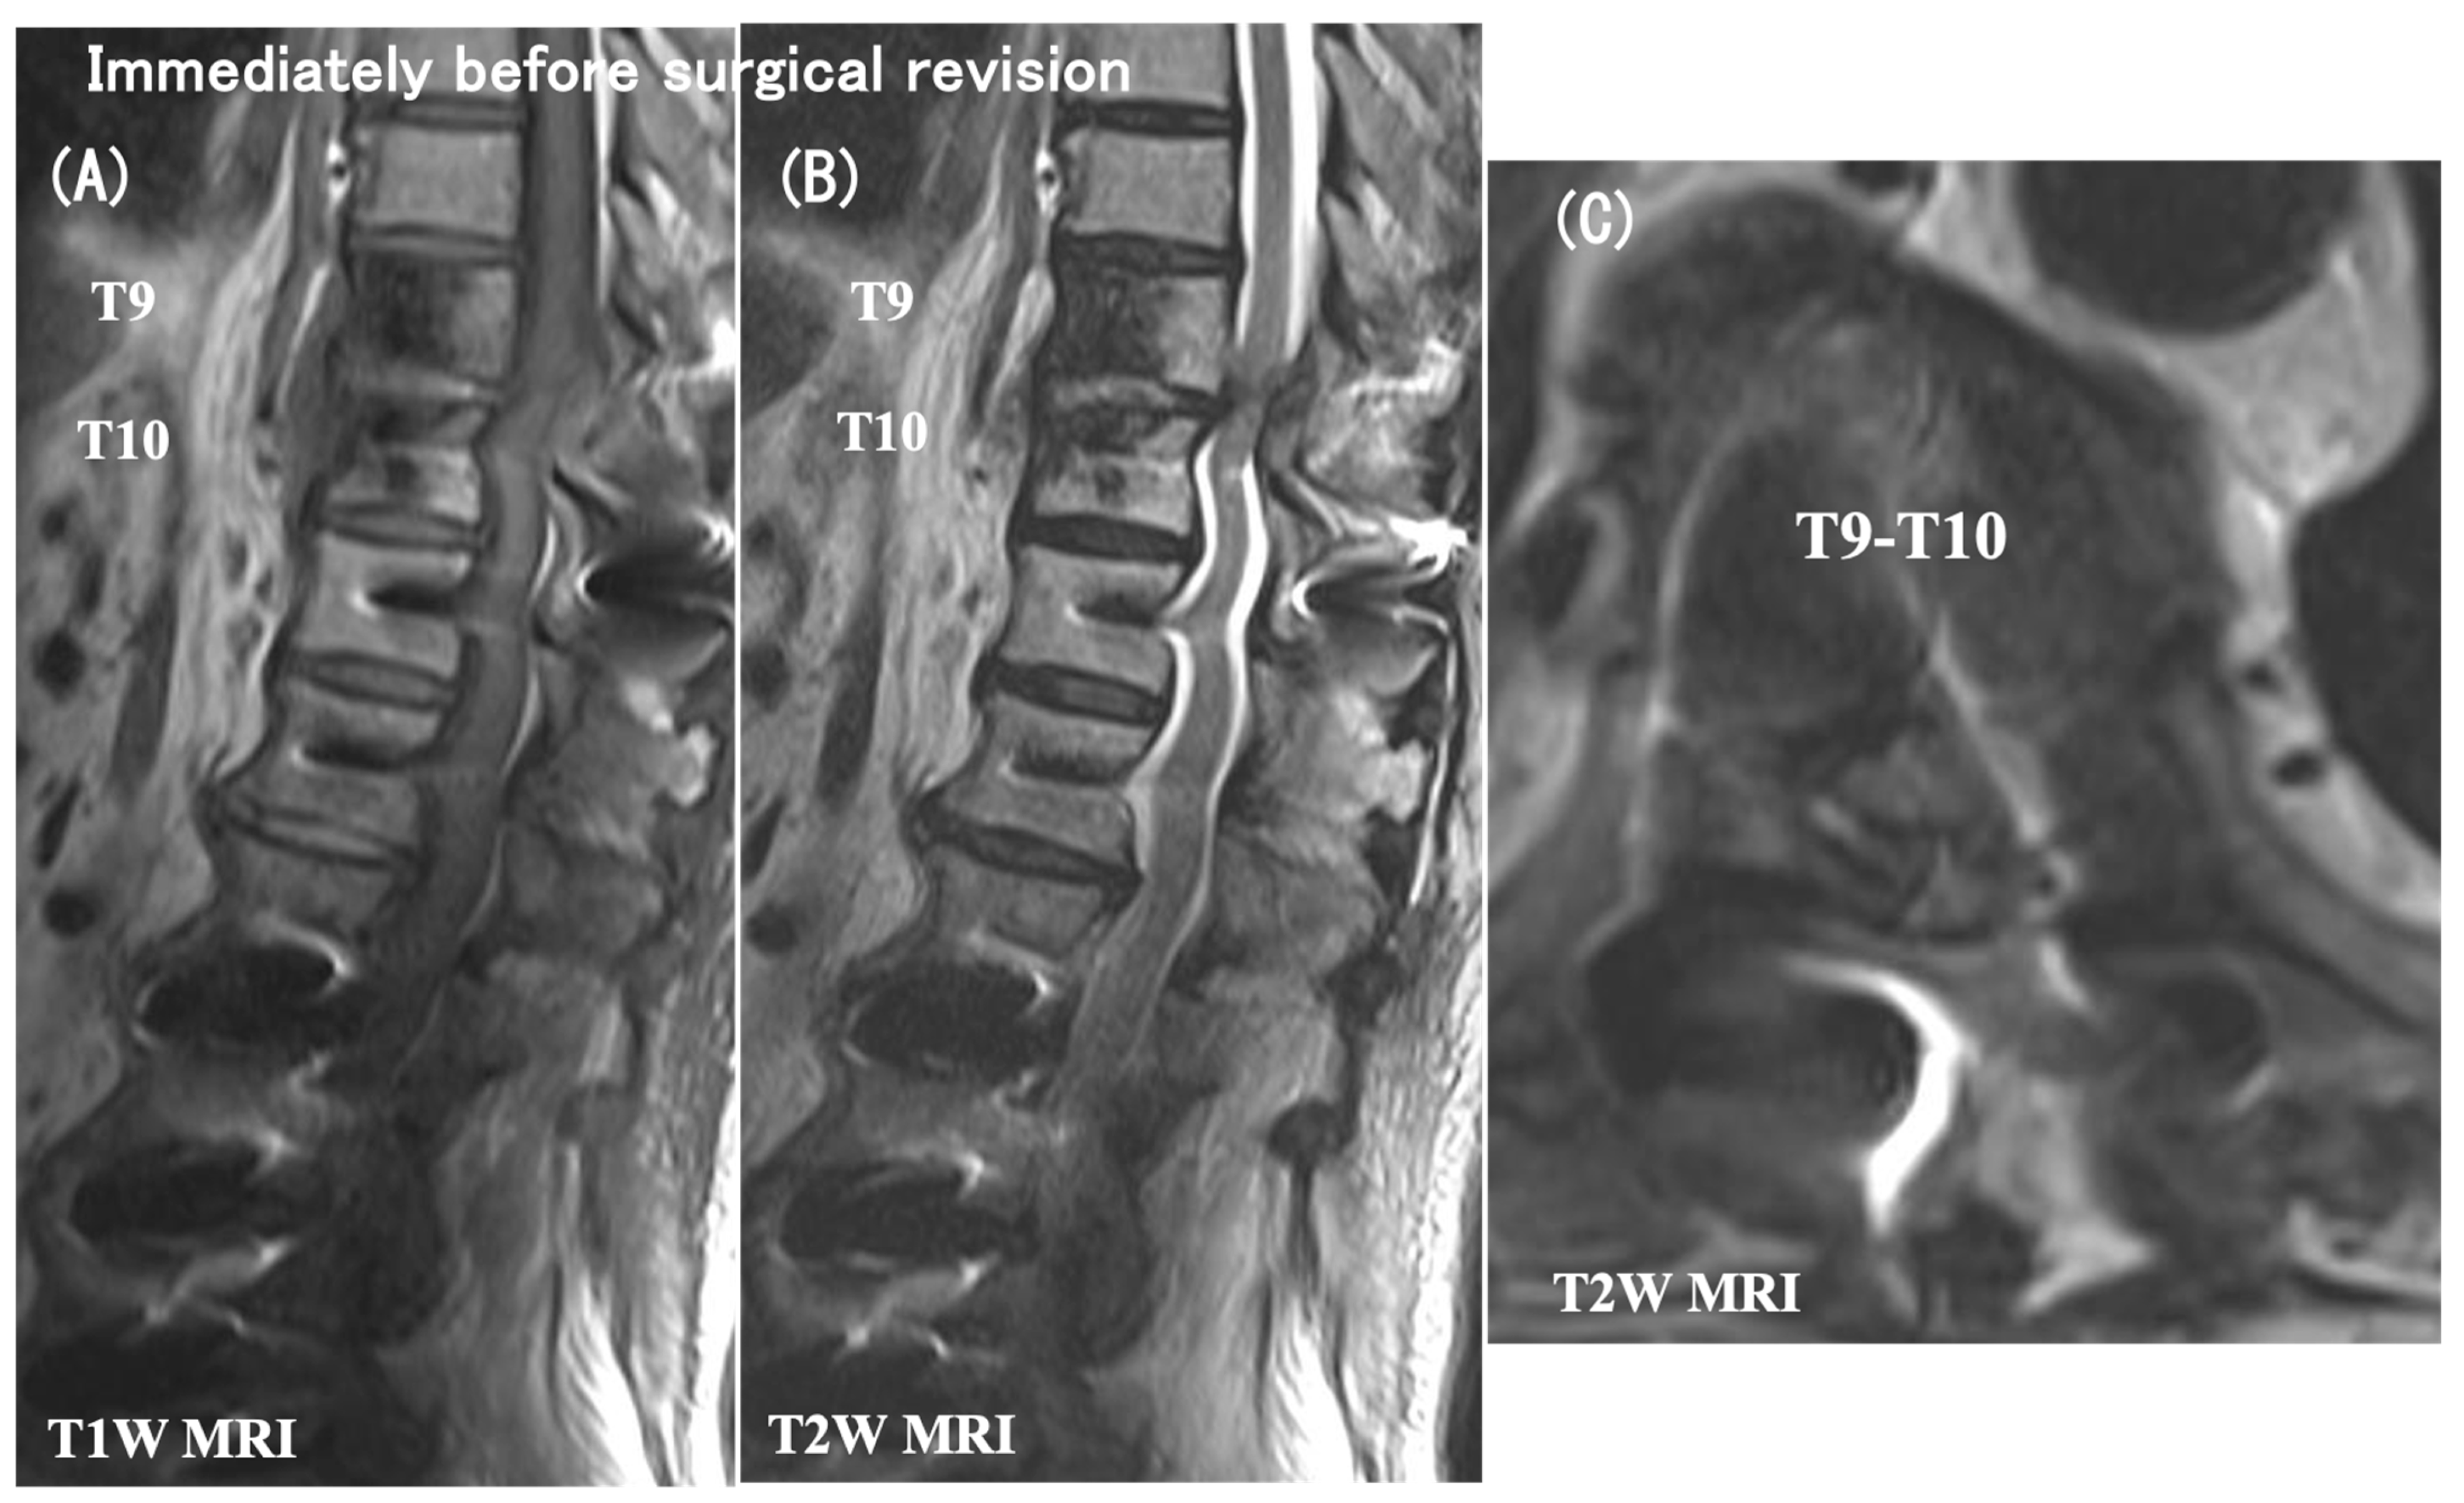

3.6. Case Presentation

- Case no. 6

- 2.

- Case no. 4